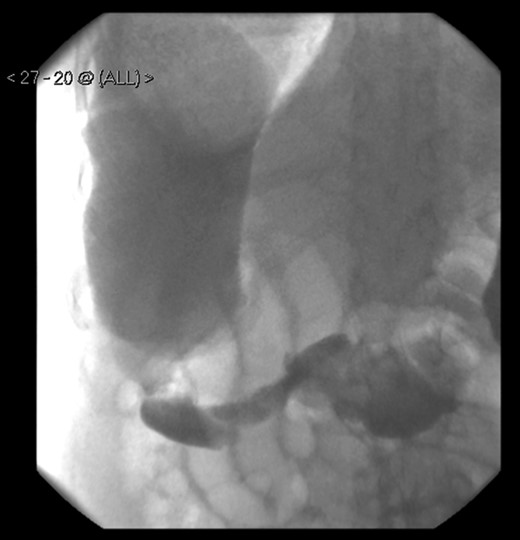

A 58-year-old female with a past medical history of a large intrathoracic hiatus hernia presented to her general practitioner and was subsequently referred to our surgical department with symptoms of sudden onset severe epigastric pain associated with vomiting and abdominal distension. Her abdomen was generally tender, maximally in the epigastric region, although she was not peritonitic. The admission erect chest radiograph showed a large hiatus hernia and an elevated right hemidiaphragm with a large loop of distended bowel (Fig. 1). Subsequent computed tomography (CT) scan demonstrated an almost completely intrathoracic stomach with a degree of volvulus, and the liver medially displaced by a loop of large bowel felt to be caecum (Fig. 2). Since the patient remained otherwise well, bidirectional endoscopy was performed, and given that a volvulus point could not be identified and the ileocaecal junction was not identified, contrast studies were requested (Figs 3–5) which demonstrated an incomplete obstruction caused by a volved caecum rotated anteriorly and cephalad.

A large bowel contrast study showing the flow of contrast from the collapsed transverse colon into the dilated, upwardly displaced caecum.